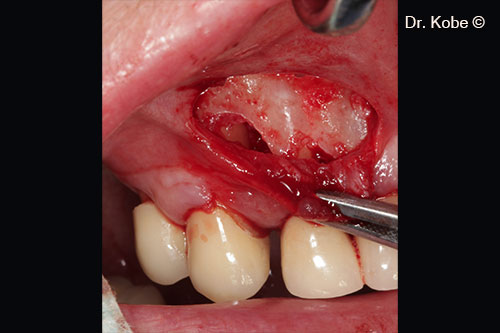

Defect filled with Gel 40